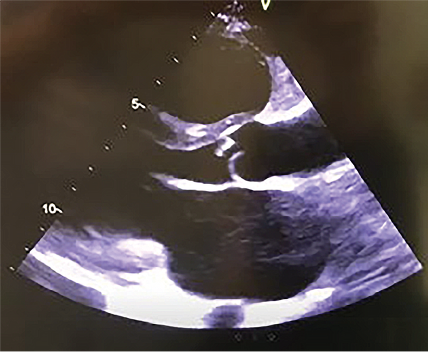

ECG: right EHA deviation, sinus tachycardia with HR 120 bpm, ST segment on the isoline. Echo: LV EF 54 %, vegetation on the aortic cusp 1.2 x 2.0 cm (Fig. 2), severe aortic insufficiency, an open abscess of the aortic root with a fistula between the aortic root and the right ventricular outflow track (Fig. 3), an open abscess of the MV anterior cusp with a developed perforation, severe insufficiency of the MV (Fig. 4). Dilation of left and right atria, moderate tricuspid valve insufficiency, stage 2 pulmonary hypertension, fluid in both pleural cavities.

Fig. 3. An open abscess of the aortic root with a fistula between the aortic root and the right ventricular outflow track

Fig. 4. Perforation of anterior cusp of mitral valve